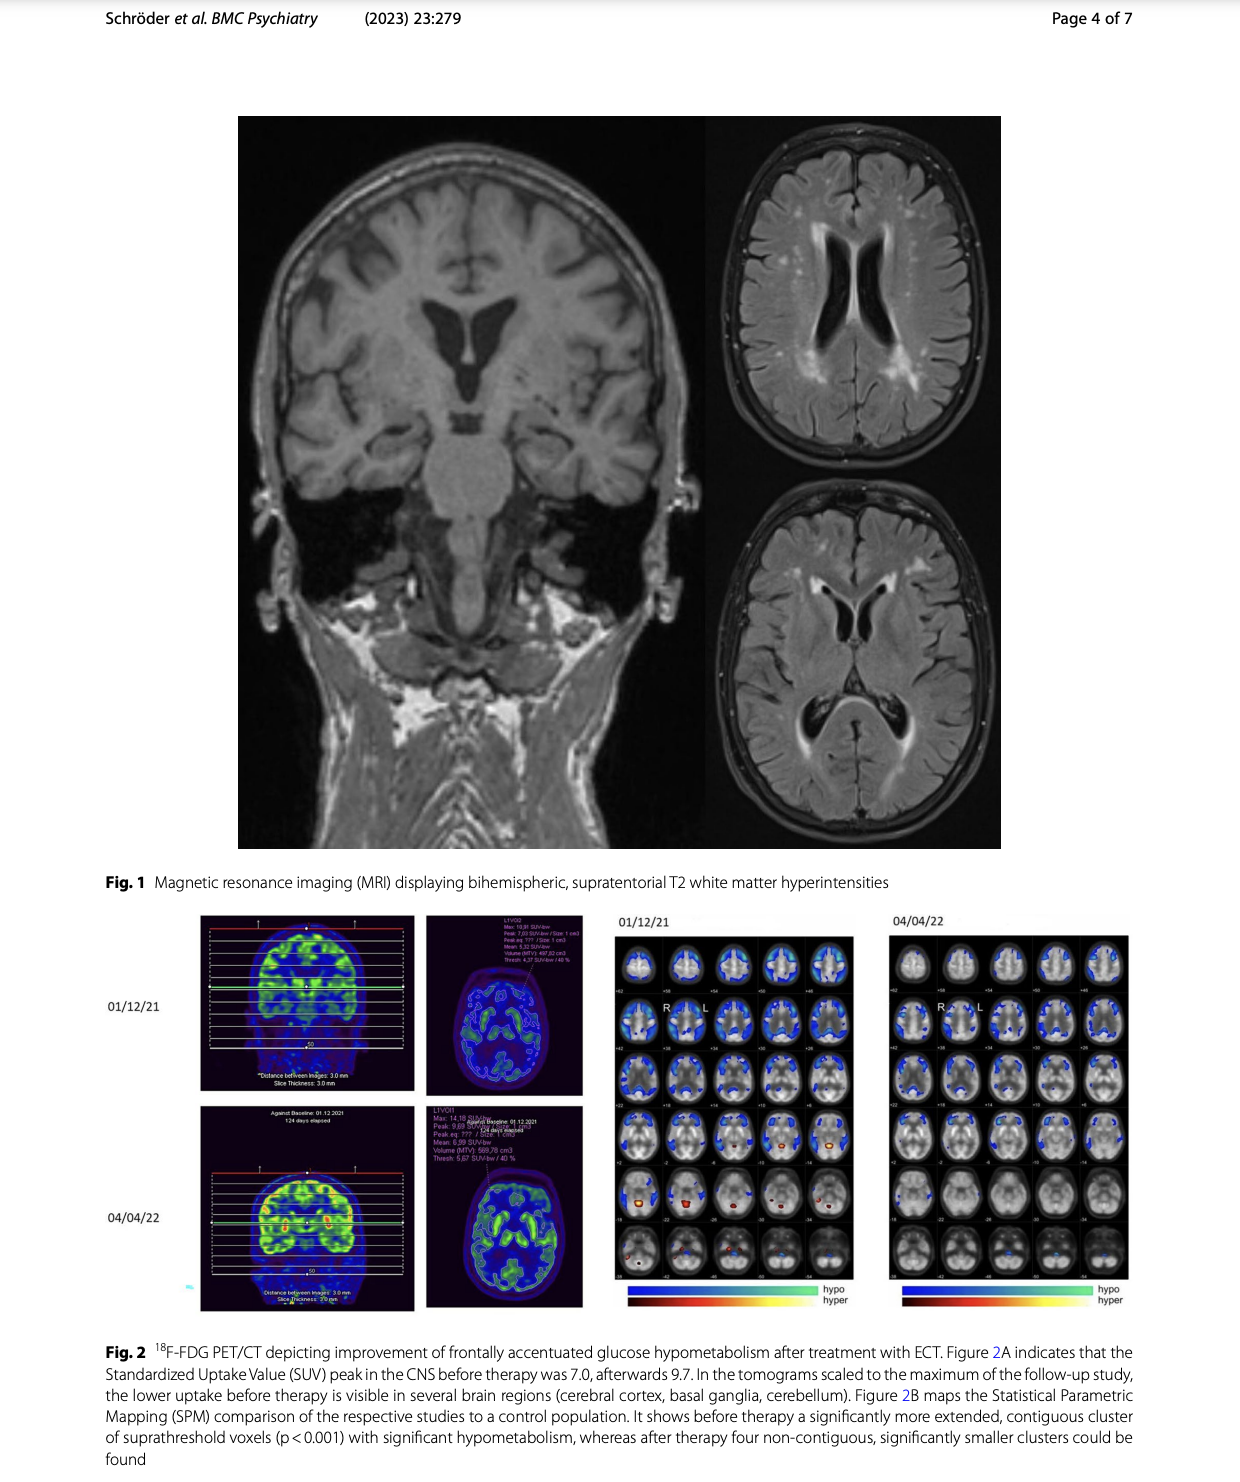

Case presentation: Here, we describe the case of a 65-year-old woman who presented to the department of psychiatry of a university hospital with depressed mood, pronounced anxiety, and nihilistic thoughts. While several pharmacological treatments remained without clinical response, further behavioral observation in conjunction with 18F-fluoro-2-deoxy-D-glucose positron emission tomography/computed tomography (18F-FDG PET/CT) revealed the diagnosis of frontotemporal dementia (FTD). To counter the pharmacological treatment resistance of psychotic depression, we decided to perform electroconvulsive therapy (ECT). Remarkably, ten sessions of ECT yielded an almost complete remission of depressive symptoms. In addition, the patient's delusional ideas disappeared. A follow-up 18F-FDG PET/CT after the ECT series still showed a frontally and parieto-temporally accentuated hypometabolism, albeit with a clear regression compared to the previous image. The follow-up 18F-FDG PET/CT thus corroborated the diagnosis of FTD, while on the other hand it demonstrated the success of ECT.

Conclusions: In this case, ECT was a beneficial treatment option for depressive symptoms in FTD. Also, 18F-FDG PET/CT should be discussed as a valuable tool in differentiating depression and dementia and as an indicator of treatment response.